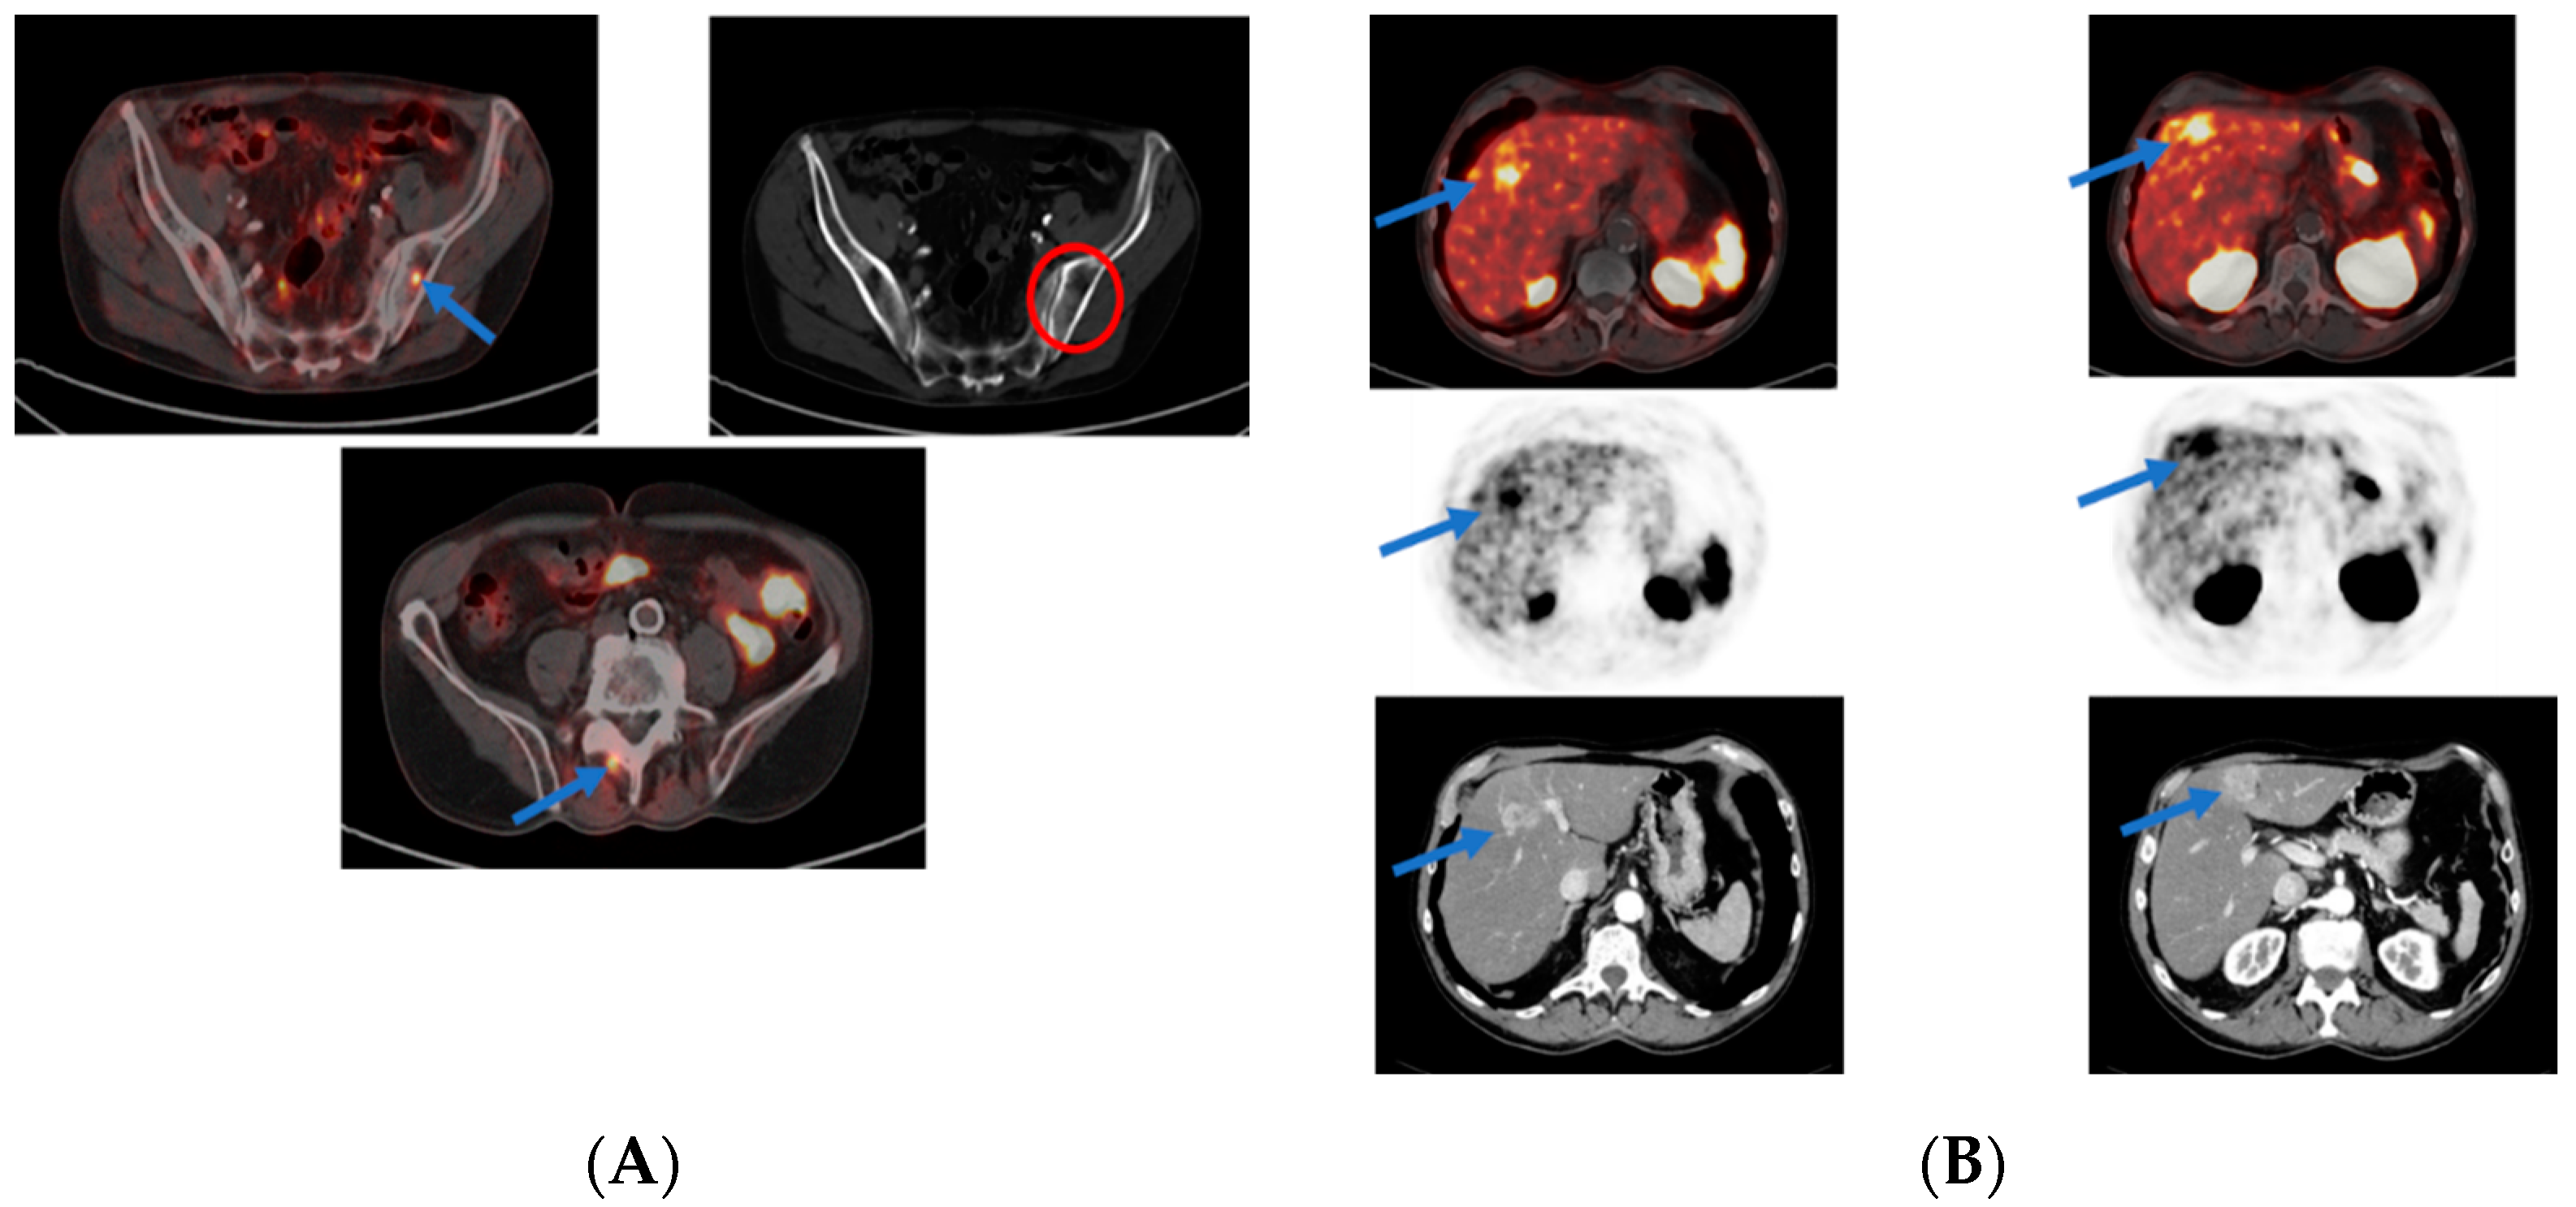

3.1. Roles of PSMA PET in Primary Staging of Prostate Cancer

3.2. PSMA PET in Biochemical Recurrence PCa

3.3. Evaluation of PCa Patients for Possibility of PSMA Radioligand Therapies